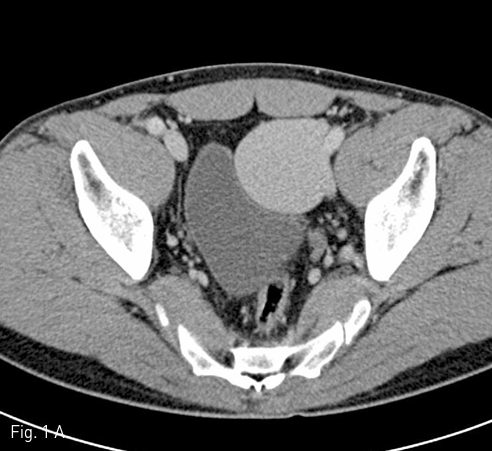

좌측 외장골정맥 aneurysm에 대한 스텐트-그라프트 설치 8개월 뒤 CT 상 aneurysm의 크기가 약 3.5 X 3.3 X 3.0 cm로 감소하였으며 (Fig. 3A), 3년 5개월 뒤 CT에서 aneurysm이 거의 남아 있지 않았다 (Fig. 3B)

Fig 3A

At 8 (A) and 41 (B) months follow-up CT show a gradual decrease in size and complete disappearance of aneurysm.